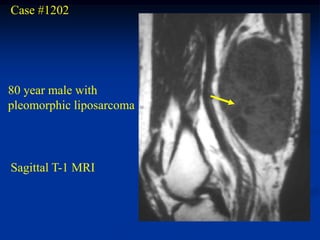

Case #1202

80 year male with

pleomorphic liposarcoma

Sagittal T-1 MRI

Sagittal T-2 MRI

Case #1202 80 yearmale with pleomorphic liposarcoma Sagittal T-1 MRI

• 255.